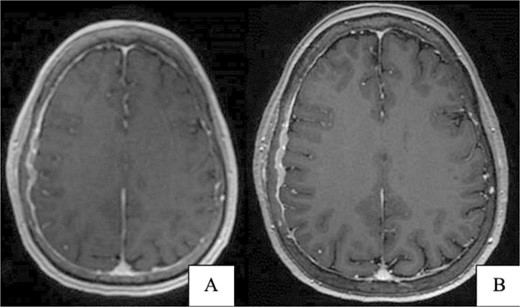

A 67-year-old female presented with transient right-sided stroke-like symptoms. The initial CT scan and MRI with and without contrast revealed a right parietal convexity heterogeneous enhancement of the calvarium with subjacent dural thickening, extending from the posterior frontal bone, concerning metastases or possibly primary osseous neoplasm. No hemorrhage or large vessel territory and no epidural mass were observed (Fig. 1). A whole-body PET-CT scan revealed heterogeneous mild to moderate abnormal fluorodeoxyglucose (FDG) uptake involving the right-sided parietal skull sclerotic lesion and no other site of abnormal uptake. She had a past medical history of right-sided breast atypical ductal hyperplasia, which was removed four years ago.

(A) Brain CT without contrast shows no acute hemorrhage or large vessel territory infarct. (B) Brain MRI without contrast: right parietal calvarial signal abnormality with subjacent dural thickening. There is no definitive parenchymal involvement.